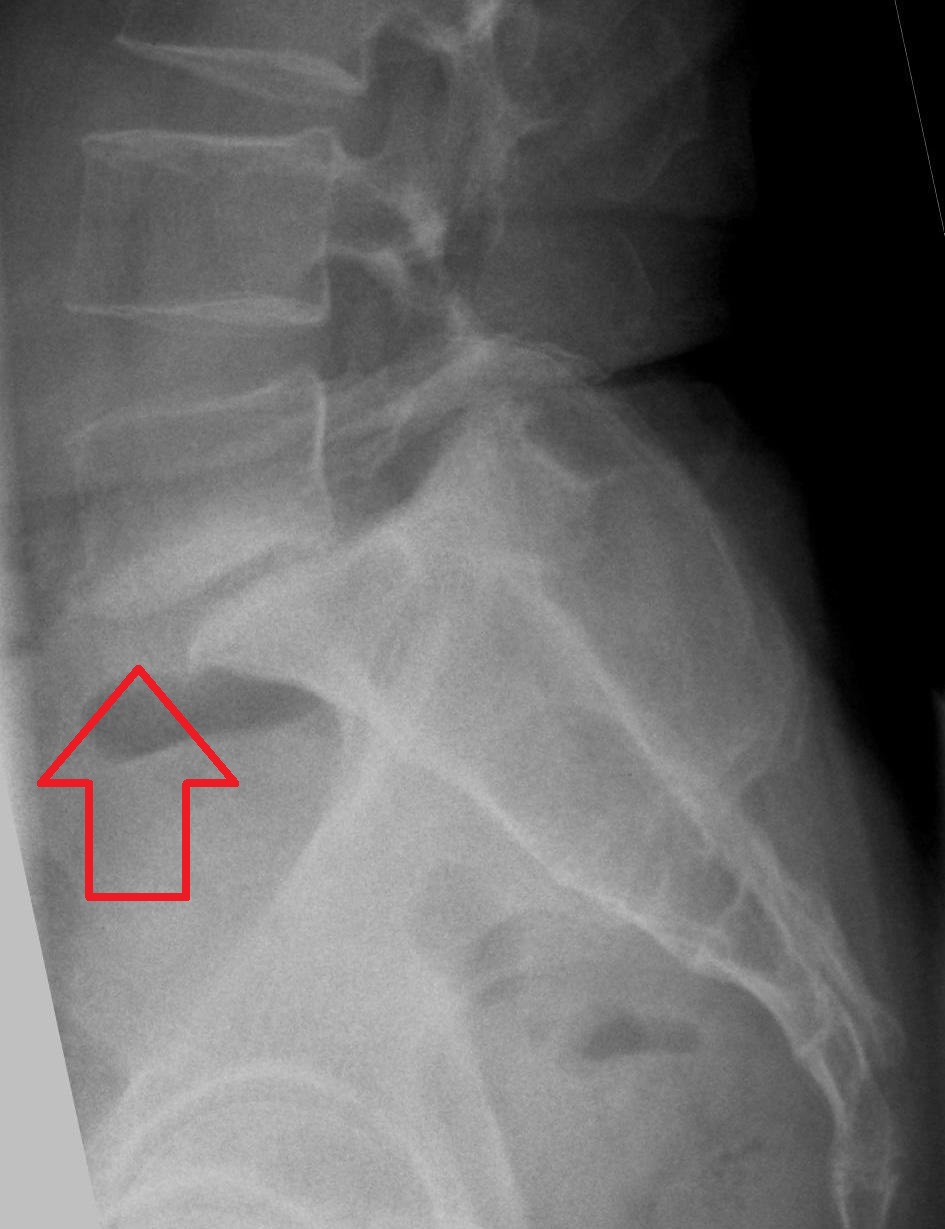

The word means spondylo = spine, listhesis = to slip. It is slippage of a vertebra over the other. This slip is seen in lower lumbar spine i.e. between L4-5, L5-S1, L3-4, Other Sites. But this listhesis can be seen so commonly in cervical spine (sometimes dorsal spine also) after major trauma.

Similar to slip / herniated disc, the diagnosis is always made by proper history (i.e. complains), check by a spine specialist and confirmed by MRI report. X-ray has great importance.